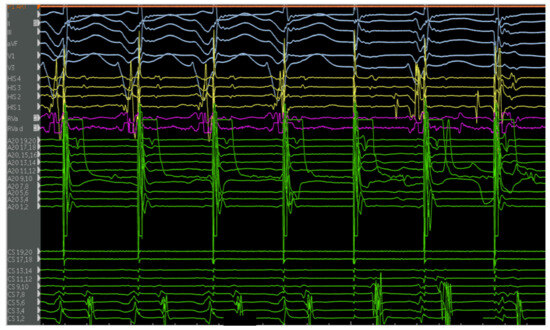

4.2. EPS and Catheter Ablation

4.2.1. Cases